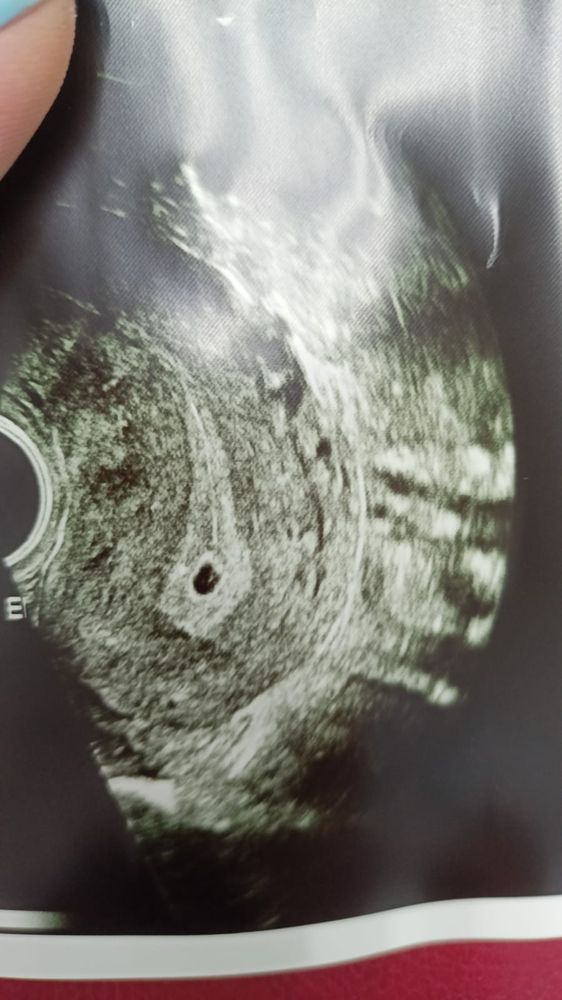

Изображение Сегодняшнее узи

01.07.2023